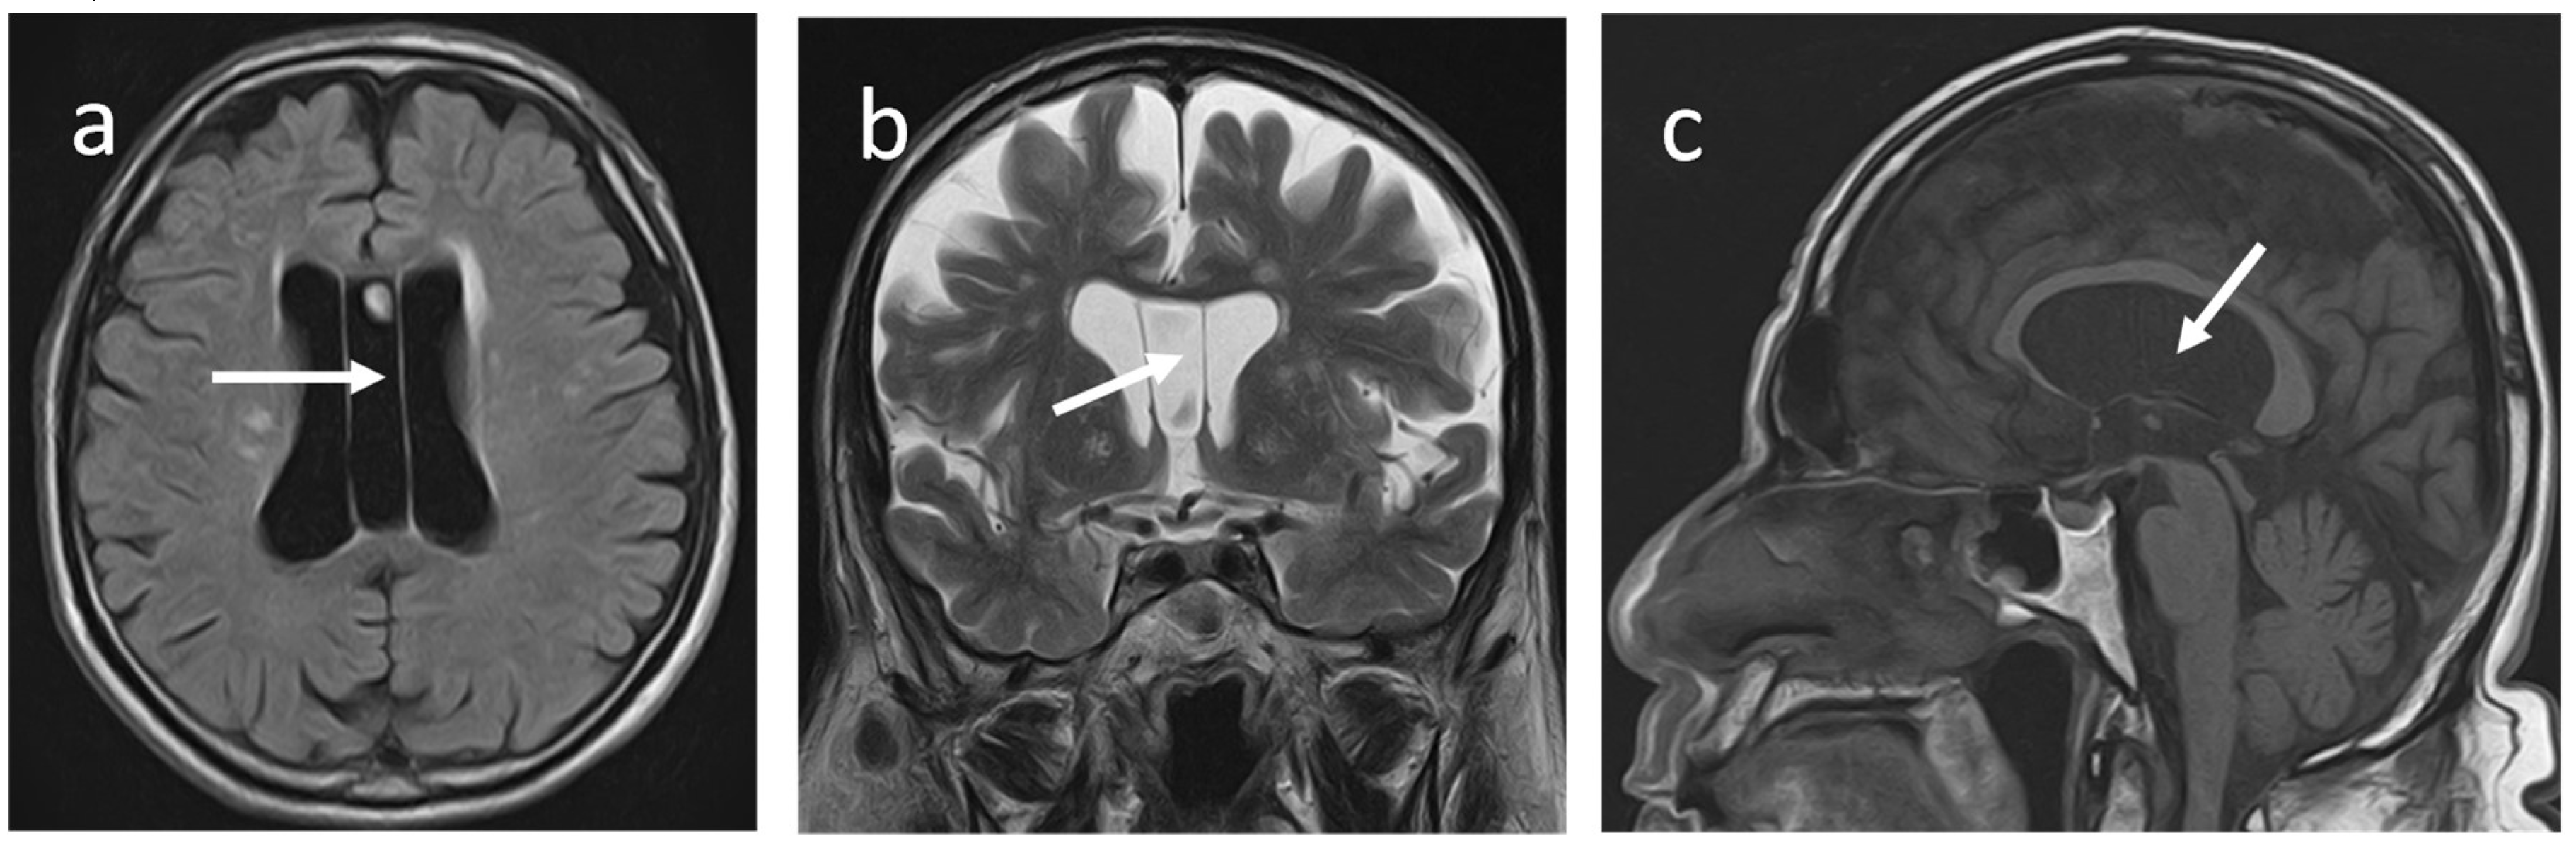

The septum pellucidum (SP) is a thin, translucent, vertical double-membrane sheet of white and grey matter between the anterior horns of the brain's lateral ventricles (1). This triangular membrane extends from the rostrum, genu, and anterior part of the body of the corpus callosum(CC) to the superior surface of the fornix (1) (Figure 1a-c).

Figure 1a-c. Normal SP anatomy on T2W-MRI of a 39-year-old male. (a) The mid-sagittal section shows the SP (green)and its boundaries. Superiorly, SP is attached to the body of CC (long arrow), Anteroinferiorly, the rostrum of the CC (short arrow) and posteroinferioly, it is attached to the columns of the fornix (arrowhead). The solid line indicates the internal cerebral vein (b)The axial (c)coronal sections show midline SP (dotted arrow) between lateral ventricles.